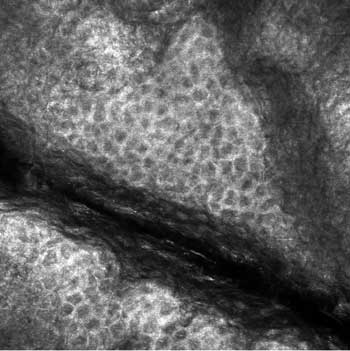

Mit der konfokalen Laserscanmikroskopie stehe eine nicht invasive In-vivo-Technologie zur Verfügung, die horizontale Schnitte der Haut mit guter zellulärer und subzellulärer Auflösung zeige (Abbildung). Das Verfahren biete die Möglichkeit, Epidermis und Dermis schichtweise von der Hornschicht bis zur oberen Dermis zu erfassen und bis zu einer Eindringtiefe von etwa 300 Mikrometer zelluläre Unregelmäßigkeiten zu evaluieren.

Konfokales Bild (500 x 500µm) des Stratum granulosum von normaler, unbehandelter Haut (In-vivo-Aufnahme mit 445nm-Laser). Die Zellkerne im Zentrum der Zelle sind als dunkle Areale dargestellt, während der zytoplasmatische Rand hell und körnig erscheint.